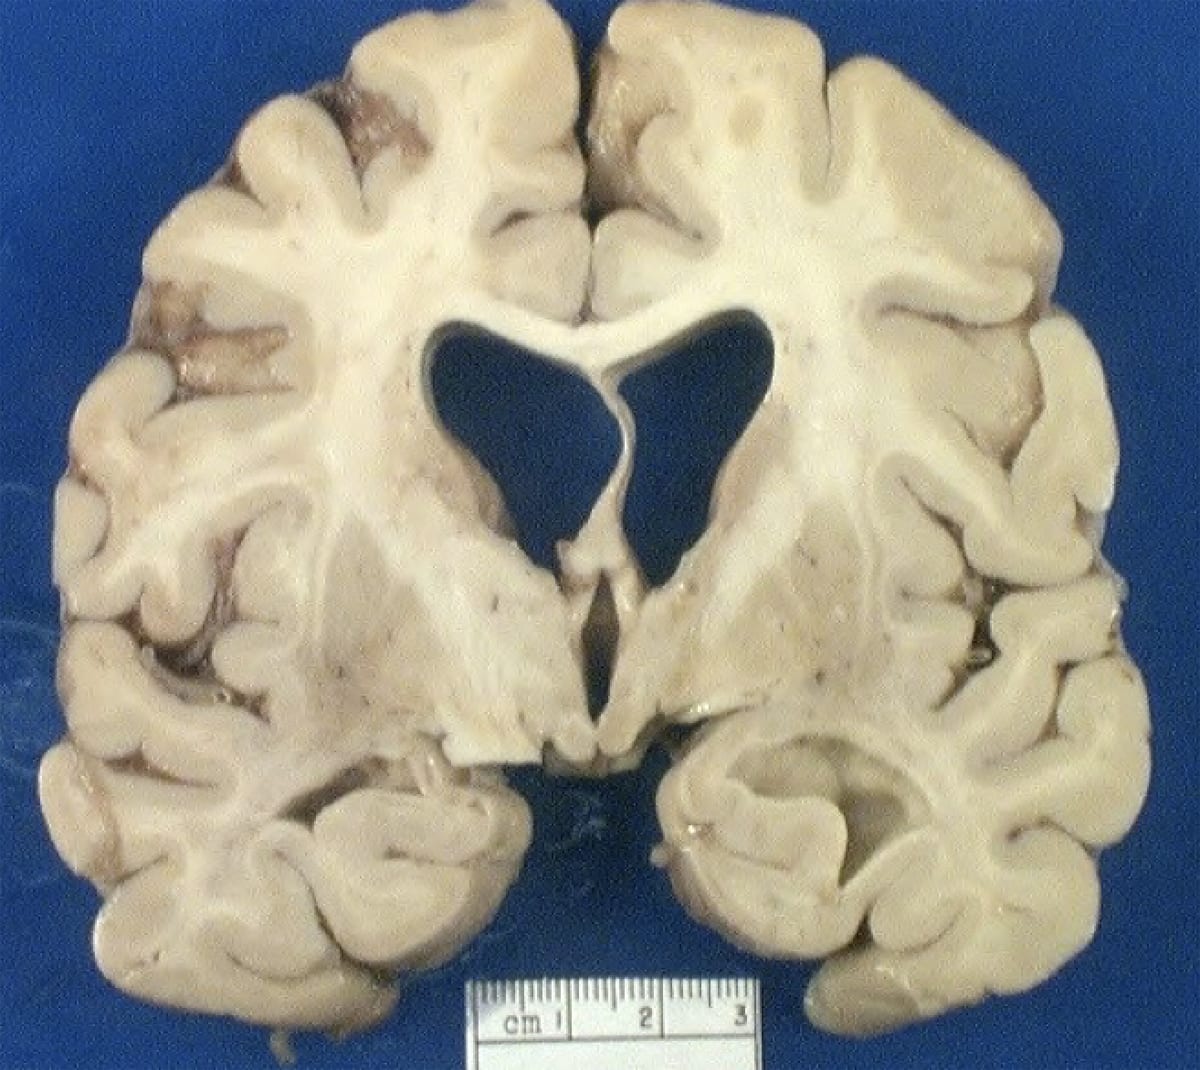

Parkinson's Disease. Midbrain on left shows pale substantia nigra.

Lewy Body (alpha-synuclein inclusions), primarily seen in substantia nigra and locus coeruleus in Parkinson's Disease.